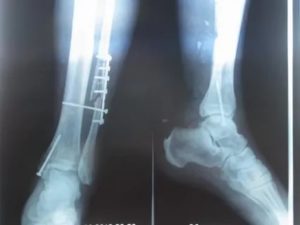

Если берцовая кость сломана на три фрагмента, травма нестабильная, открытая, а консервативная терапия неэффективна, целесообразно отдать предпочтение хирургическому вмешательству.

- Среди многообразия эффективных методик стоит выделить интрамедуллярный остеосинтез. Операция предполагает внедрение внутрисуставного крепежного штифта в полость поврежденной кости. Штифт будет удерживать сломанные осколки до тех пор, пока костная ткань не срастется. На противоположных сторонах кости он фиксируется за счет винтовых соединений, благодаря чему фиксация даже крайне сложных переломов становится возможной. Поскольку в детском возрасте кости некоторое время продолжают расти, данный метод на юных пациентах неприменим;

- Альтернативой может стать наложение винтов и пластин с предварительным соблюдением последовательности восстановления расположения кости;

- В крайних случаях можно прибегнуть к наружной фиксации. Специальные шурупы вживляются в кость с последующим наружным выведением. Фиксация происходит посредством конструкции из металла, которая предотвращает смещение осколков и обеспечивает надежную фиксацию. Для длительной реабилитации при работе с детьми такая методика не подходит.

Если вытяжение не приносит должного результата, то больному назначается оперативное вмешательство, во время которого костные отломки фиксируются с помощью стержней, шурупов, пластин или аппарата Илизарова.

Стержень

В коже пациента производится разрез, сквозь который в канал кости вставляется стержень из медицинской стали. Стержень вынимается, когда кость полностью срастается.

Пластина

В коже делаются отверстия, и к кости с помощью специальных саморезов прикручивается пластина. Данная операция не проводится при переломе голени у детей, потому что во время нее может повредиться надкостница, что негативно скажется на процессе роста кости.

Шурупы

Когда случается продольный перелом, кости соединяются и фиксируются шурупами, которые удаляются после срастания отломков.

Аппарат Илизарова

Этот метод считается самым надежным для быстрого лечения, поскольку спицы вставляются в костные отломки и выводятся наружу, образуя каркас. Кости фиксируются жестко, доктор имеет возможность изменять положение сегментов во время лечения.